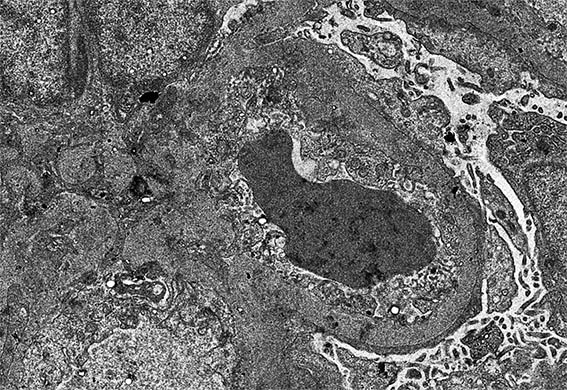

Figura 12. ME, aumento original, X2.100.

Figura 13. ME, aumento original, X4.000.